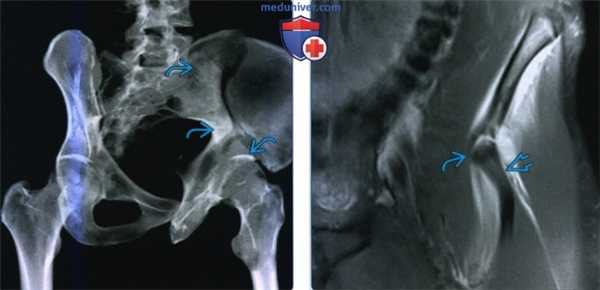

(Слева) КТ, 3D реконструкция подвздошной проекции Жюде: определяется изолированный перелом крыла подвздошной кости (Дювернье) вследствие удара о дерево при катании на лыжах. Несмотря на распространение перелома в соседнюю губу вертлужной впадины, повреждение сустава отсутствует.

(Справа) МРТ, PDВИ, режим подавления сигнала от жира, коронарный срез: определяется отрыв передней нижней ости подвздошной кости, ниже места прикрепления прямой головки прямой мышцы бедра. Костные отрывы в области прикрепления сухожилий таза возникают почти исключительно у пациентов с незрелым скелетом, в то время как у взрослых наблюдаются травмы сухожилий.

2. Рентгенография при изолированной травме таза:

• Передне-задняя проекция таза в большинстве случаев является методом выбора:

о Тазовое кольцо не разрывается в двух местах

• Изолированный перелом крыла подвздошной кости:

о Обычно крупный костный осколок с минимальным смещением

о Подвздошно-седалищная и подвздошно-лобковая линии не повреждены

о Для исключения поражения вертлужной впадины может быть выполнена КТ